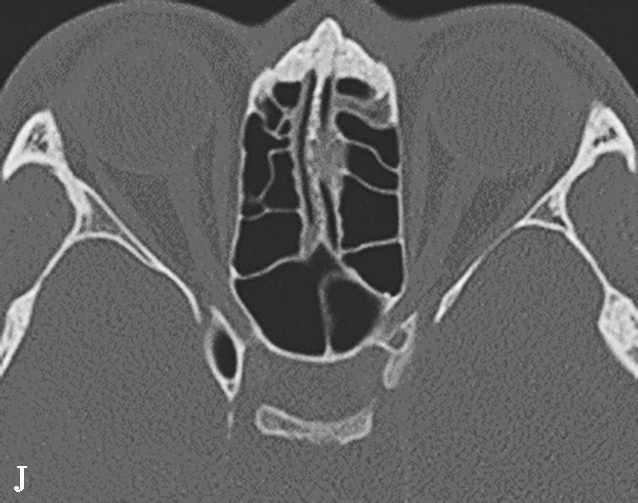

图1-3-7 蝶窦及蝶窦区解剖变异

A.颈内动脉管突入蝶窦;B.蝶窦间隔(白箭);C.左侧翼突气化;D.蝶嵴(星)、蝶骨大翼(白箭)、鞍背气化(虚箭);E.蝶骨小翼气化(白箭);F、G.鞍前型蝶窦(三角);H、I.甲介型蝶窦;J、K.鞍型蝶窦;L.Odoni气房(白箭)